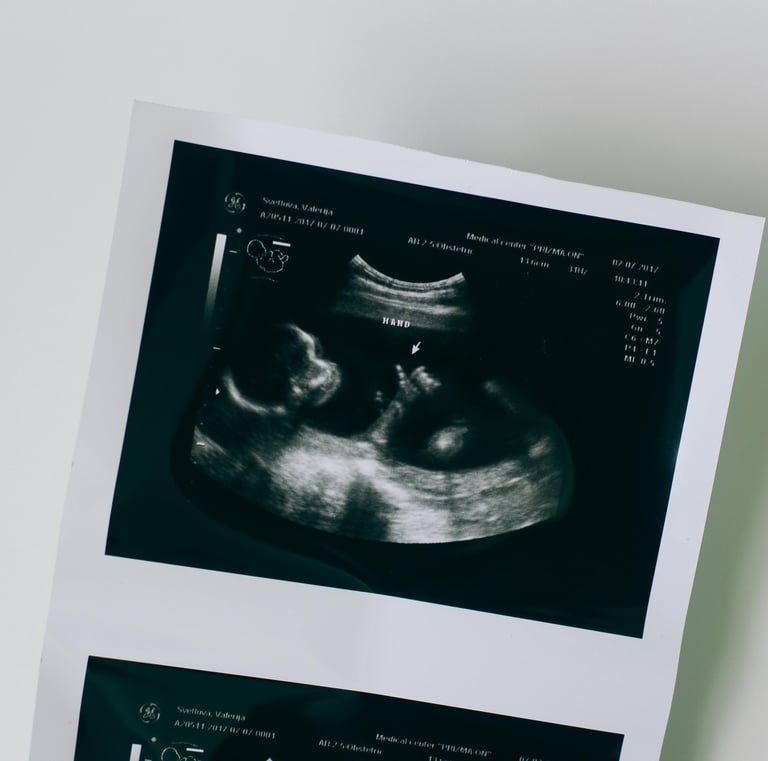

El ultrasonido es una técnica de diagnóstico seguro, no invasivo y libre de radiación, ampliamente utilizado en diversas áreas de la medicina como ginecología, obstetricia, urología, medicina interna y músculo-esquelético.

Sirve para detectar enfermedades, evaluar el desarrollo del embarazo y dar seguimiento a condiciones crónicas, permitiendo diagnósticos tempranos y decisiones clínicas más precisas.

Galería Médica

Explora nuestro servicio de ultrasonido y estudios clínicos por imagen.